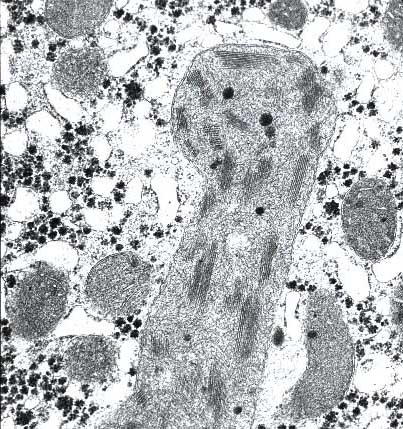

li-8-4-16.jpg (75249 bytes)

Fig. 8-4-16:

Giant Mitochondria